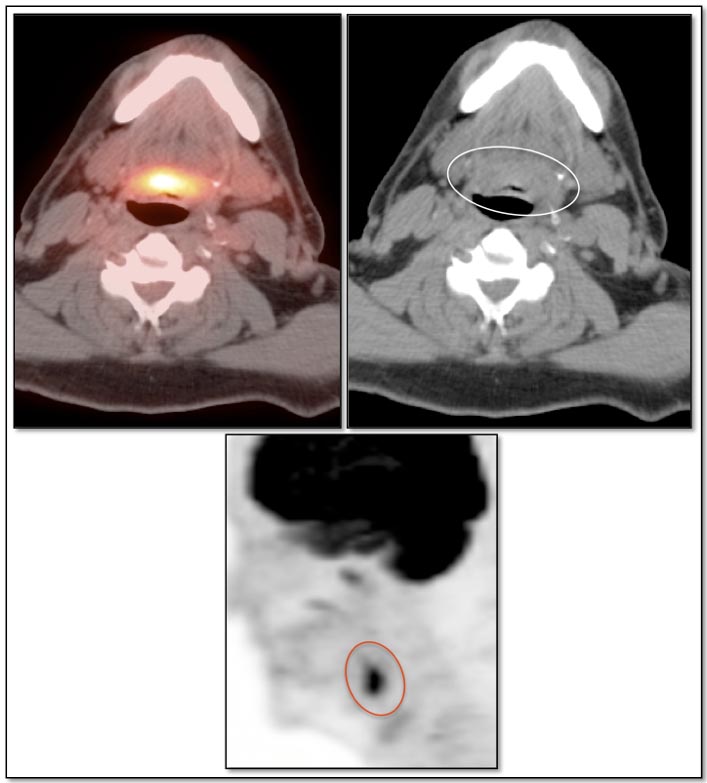

Focal, eccentric or asymmetric uptake along a portion of the tongue base should always raise a concern for a primary tongue base cancer, and requires direct visualization by a clinician (addressed in detail, here).